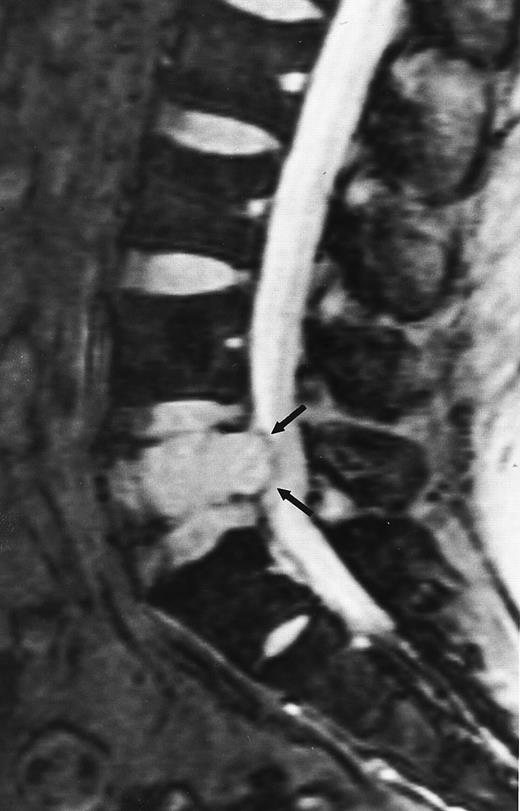

An 82-year-old man with multiple myeloma and cord compression. T2-weighted, fat-suppressed fast spin echo (5000/96, TR/TE, ET16) sagittal MR image of the thoracic spine shows abnormal signal in several compressed vertebral bodies (arrows). The spinal cord (c) is severely compressed by epidural mass (m).